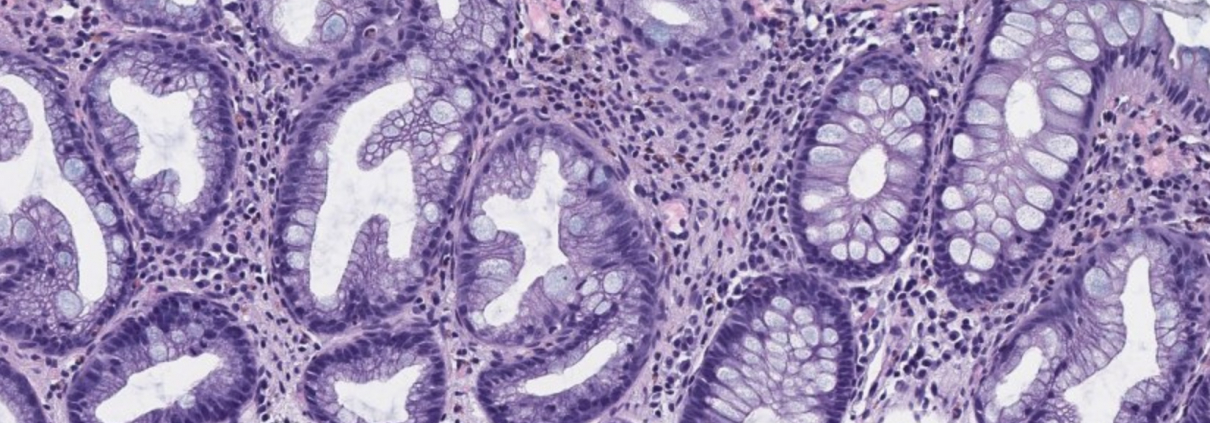

Mikroskopische Untersuchung von Gewebe (mit dem Mikroskop): Nach Aufarbeitung der auffälligen Gewebsareale durch das technische Personal werden die Präparate unter dem Mikroskop angeschaut. Sieht das Gewebe normal aus? Ist es entzündet? Findet man seltsam aussehende Zellgruppen, die weiter untersucht werden müssen? Dies geschieht mit einer bis zu 400x-fachen Vergrößerung bei der Begutachtung am Mikroskop.

Histochemische Untersuchung von Gewebe (Darstellung bestimmter Substanzen): Um auffallende Zellgruppen besser einzuordnen, können am Schnittpräparat mithilfe verschiedener chemischer Reaktionen beispielsweise Schleim oder auch Bakterien nachgewiesen werden.

Immunhistochemische Untersuchung von Gewebe (Darstellung von bestimmten Eigenschaften von Zellen): Die auffälligen Zellgruppen werden weiter untersucht, indem bestimmte Zelleigenschaften angefärbt werden. So kann herausgefunden werden, ob es sich beispielsweise um Krebszellen handelt und von welcher Sorte die Krebszellen sind. Oft kann hier schon bestimmt werden, ob eine spezielle Therapie für diese Krebsart geeignet ist.